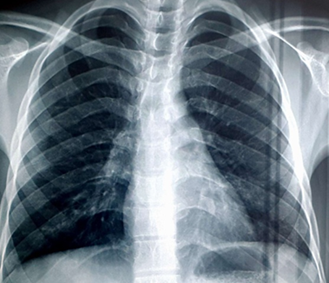

The chest X-ray revealed a diffuse bilateral alveolo-interstitial syndrome, filling both lung fields (Figure 2), in contrast to the initial chest X-ray (before methotrexate treatment), which was normal (Figure 1).

Figure 1: Chest X-ray Before Treatment.